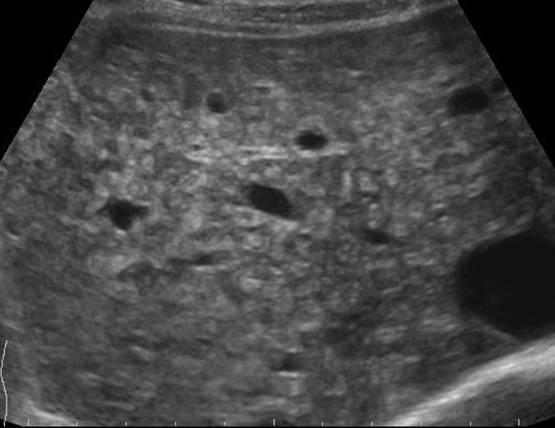

Hamartoma đường mật

» Thông tin: Nam giới – 34 tuổi.

» Lâm sàng: Kiểm tra sức khỏe.